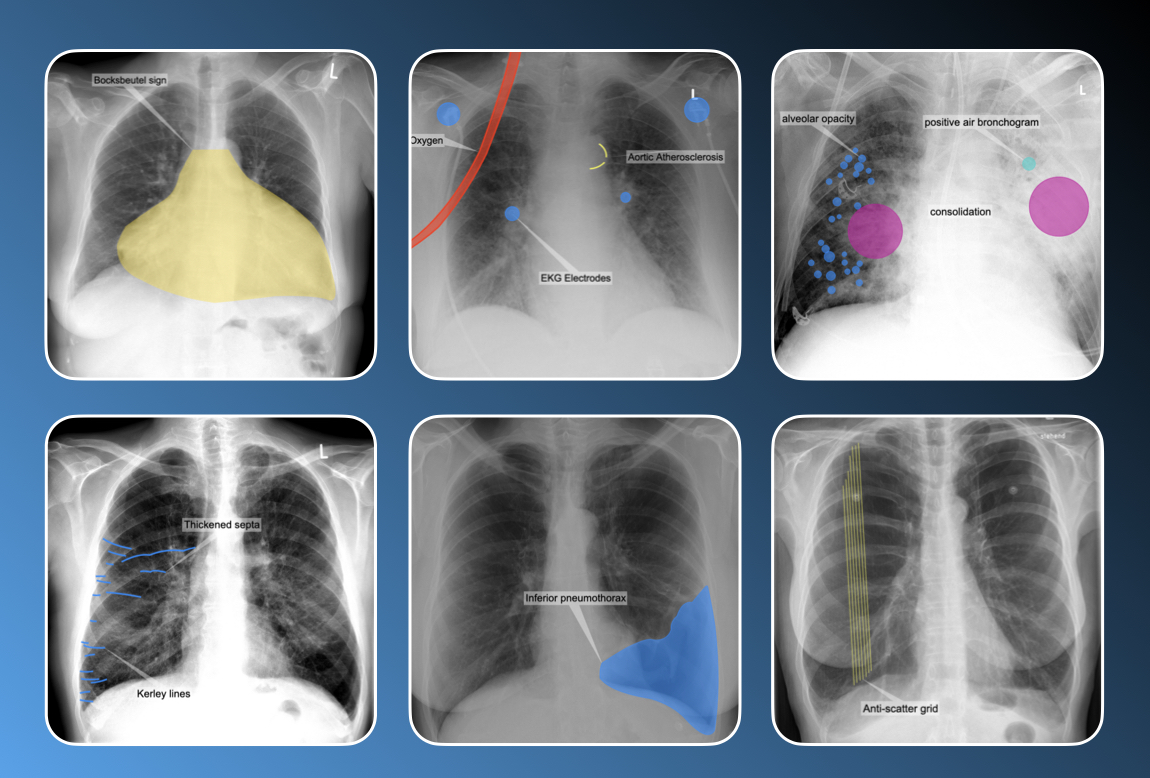

Chest X-ray Trainer | Part 2

18

35

Chest X-ray Trainer | Part 3

24

54